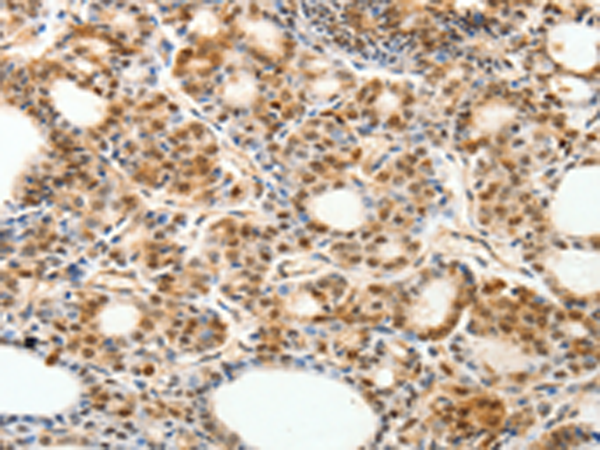

分类: 科研抗体货号: P07511别名: RK; p38; CSBP; EXIP; Mxi2; CSBP1; CSBP2; CSPB1; PRKM14; PRKM15; SAPK2A; p38ALPHA应用: IHC反应种属: Human, Mouse, Rat